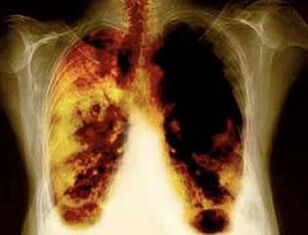

- An der Period vun 2 Wochen op 3 Méint no der Oflehnung vu Fëmmen, d'Aarbecht vun de Longen verbessert an en Ausstäerkte ass gefillt.

- No 1 -99 Méint, Houscht a Kuerz Otem stattfonnt: Cilia (kleng Haeren) fänken normalerweis fir d'Lunge fir d'Lunge fir de Risiko ze reduzéieren.

- 10 Joer no der Komaterinatioun vum Citrofis vun der Longem Kriibs ofgeholl ginn.